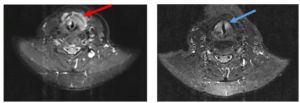

Ca lâm sàng: Điều trị bệnh nhân ung thư phổi di căn xương tại Trung tâm Y học hạt nhân và Ung bướu, Bệnh viện Bạch Mai GS.TS. Mai Trọng Khoa, PGS.TS. Phạm Cẩm Phương, BSCKII. Lê Viết Nam, BSNT. Vũ Thị Niên Trung tâm Y học hạt nhân và...